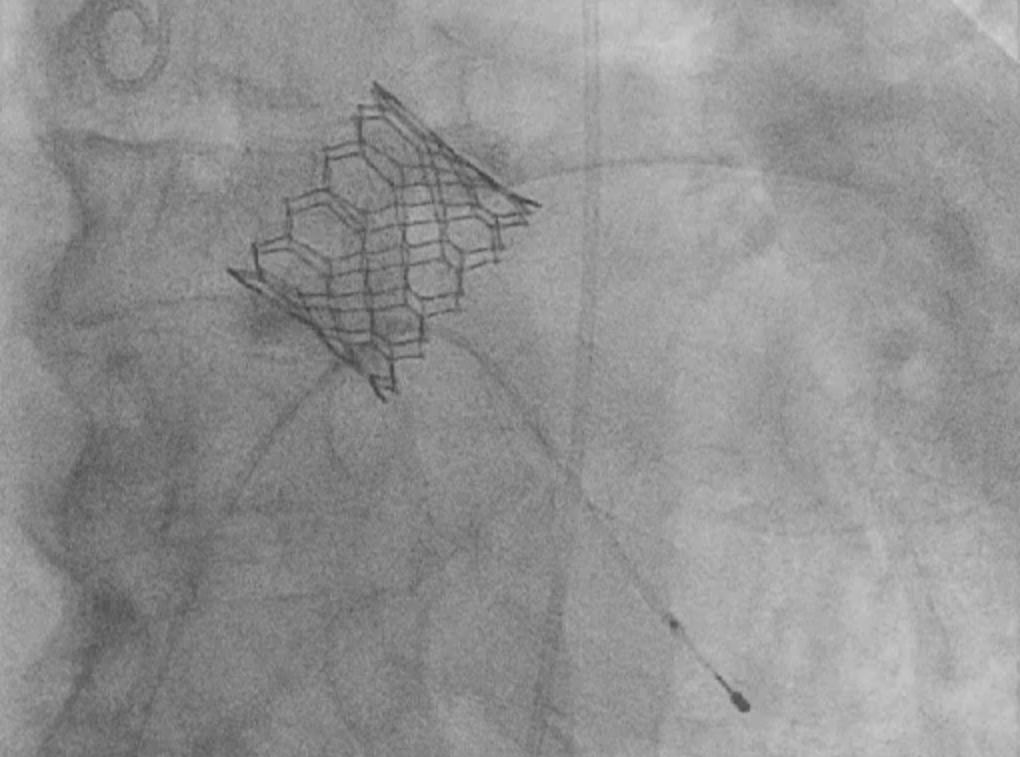

Bei dem Eingriff durch unser erfahrenes Klappenteam wird die neue Herzklappe rückwärts über die Leistenarterie entlang  der Hauptschlagader  mit einem Katheter in die Position der verkalkten Aortenklappe vorgebracht. Sobald sich die Klappenprothese in exakter Position befindet, wird sie implantiert. Der Eingriff erfolgt in Lokalanästhesie.

In unserer Kardiologie implantieren wir sowohl ballonexpandierende wie auch selbstexpandierende/re-platzierbare biologische Aortenklappenprothesen.